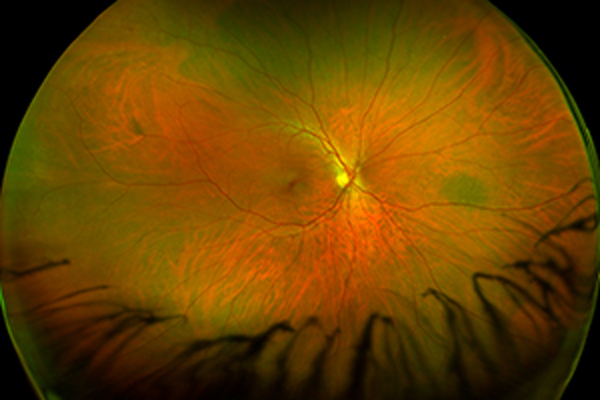

Die Untersuchung der Netzhaut ist zur Klärung vieler Fragestellungen in der Augenheilkunde essenziell. Ohne Hilfsmittel wie Augentropfen oder spezieller Optiken ist nur ein kleiner zentraler Ausschnitt der Retina zu untersuchen. Grund hierfür ist die lichtreagible Pupille welche sich, in Analogie zu einer Lochblende, bei Untersuchung mit einer Lichtquelle (z.B. Spaltlampe) zusammenzieht und eng stellt. Um eine Untersuchung der gesamten Netzhaut bis in die Randbereich zu ermöglichen, muss die Pupille mit Augentropfen medikamentös erweitert werden.

Eine Untersuchung ist auf diese Weise sehr gut möglich, jedoch sind Sie durch die Weitstellung der Pupille nicht nur lichtempfindlich, sondern auch die Akkommodation sowie die Sehschärfe sind herabgesetzt. Die Fähigkeit zur aktiven Teilnahme am Straßenverkehr und die Bedienung von Maschinen ist dadurch beeinträchtigt und deshalb erst 4 Stunden nach Applikation der Augentropfen wieder möglich, sehr selten noch später.

In den meisten Fällen ist die Untersuchung mittels einer speziellen Ultra-Weitwinkel Kamera eine komfortable Alternative. Die berührungslose Aufnahme ermöglicht eine nahezu vollständige Untersuchung der Retina - die Gabe von Augentropfen ist nicht notwendig, so dass Sie im Anschluss keinerlei Einschränkungen haben.

Sprechen Sie uns an, ob diese Untersuchung in Ihrem Fall sinnvoll ist.

Aktuell können wir Ihnen diese Untersuchung nur in der Praxis Fulda Innenstadt anbieten.

Optos Ultra-Weitwinkel Netzhautuntersuchung